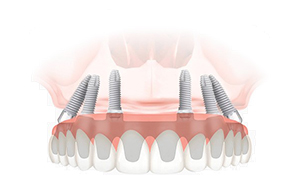

Что такое имплантация

по методу All-on-4?

Суть метода «все на четырёх» в опоре конструкции на 4, особенным образом установленных имплантата, взамен традиционной опоры на 6 или 8 имплантатов. Это позволяет восстановить жевательную функцию с меньшими затратами и без операций по наращиванию костной ткани. Такая технология обеспечивает устойчивость конструкции, предотвращает смещение при пережевывании пищи и не требует длительного послеоперационного ухода.